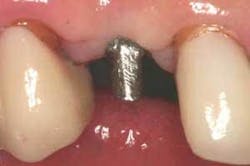

Figure 7 - Abutment prepared to tissue height. The abutment is prepared using a medium grit diamond to provide a course surface, which enhances micromechanical lock to the cement.